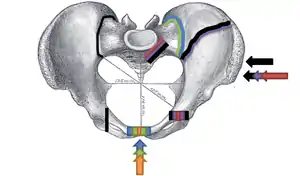

Open book fracture

One specific kind of pelvic fracture is known as an 'open book' fracture. This is often the result of a heavy impact to the groin (pubis), a common motorcycling accident injury. In this kind of injury, the left and right halves of the pelvis are separated at front and rear, the front opening more than the rear, i.e. like an open book that falls to the ground and splits in the middle. Depending on the severity, this may require surgical reconstruction before rehabilitation.[11] Forces from an anterior or posterior direction, like head-on car accidents, usually cause external rotation of the hemipelvis, an “open-book” injury. Open fractures have an increased risk of infection and hemorrhaging from vessel injury, leading to higher mortality.[12]